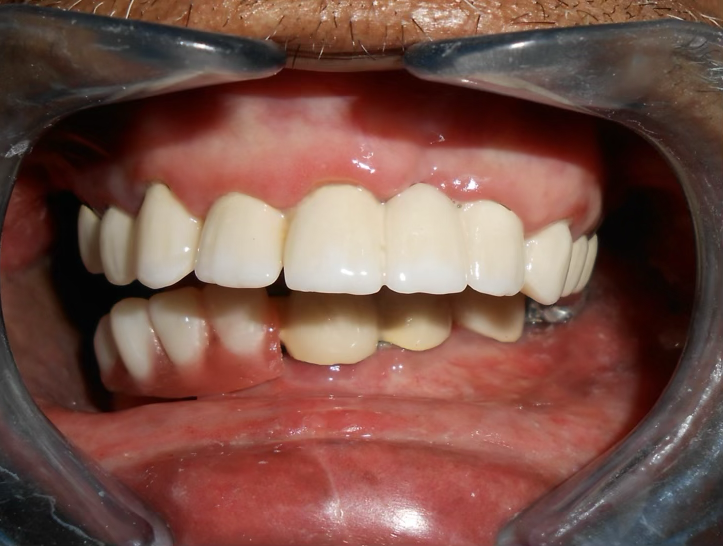

Final result

A 72-year-old male oral cancer survivor visited our dental center after surgical removal of the right side of his mandible. Patient had multiple missing and attrited teeth with significant functional impairment. Treatment involved implant-supported lower teeth with PFM crowns and precision-attached removable denture for hemimandibulectomy rehabilitation.

PFM crowns were fabricated and fixed for the upper remaining teeth to restore function and aesthetics.

Implants were delayed loaded after 3 months with PFM crowns. Precision-attached metal removable denture was inserted for comprehensive hemimandibulectomy rehabilitation.

"After my cancer treatment and jaw surgery, I thought I would never eat or speak normally again. This team gave me hope and delivered results beyond my expectations. I can eat, talk, and smile with confidence."

— Patient (72 years, Male) - Cancer Survivor